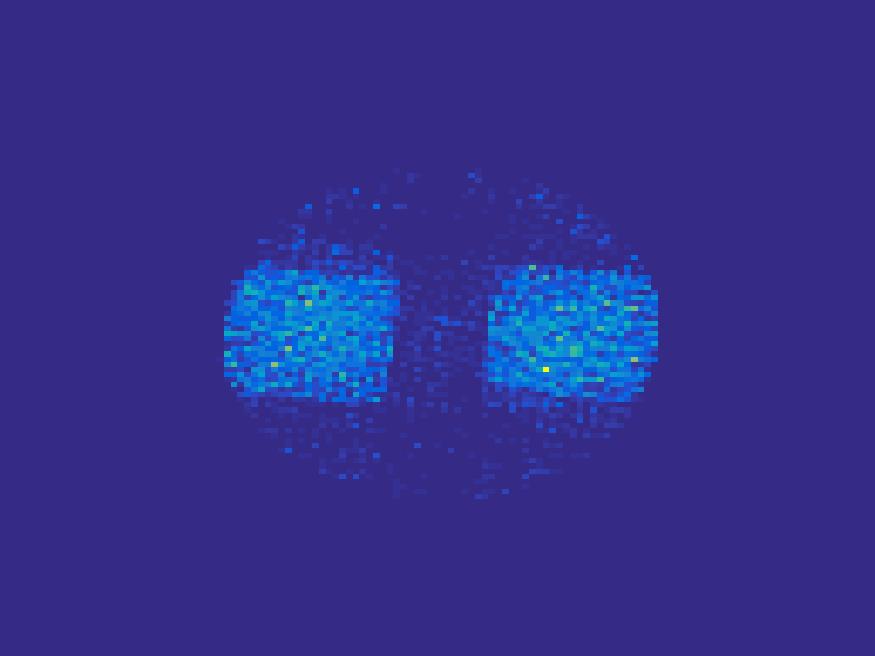

The proposed method is tested on numerical phantoms for a proof of concept study. We simulate image frames of size and projections per frame. Three time activity curves (TAC) for blood, liver and myocardium, previously used in [14] (see Figure 1), are used to simulate the dynamic images. The first simulated dynamic phantom is composed of two ellipses. In temporal direction, the positions of the two ellipses are stationary while the intensity in 90 frames within the region of each ellipse is generated according to the TAC of blood or liver. The projections are generated by using Radon transform sequentially performed for each frame.

In the tests, projections at two orthogonal angles are simulated for every frame to mimic 2-head camera data collection. The projection angles increase sequentially by along temporal direction. For example, at frame 1, projections are simulated at angle and , and at frame 2, angle and , etc. Finally, white Gaussian noise is added to the projection data. Reconstruction results with different methods are shown in Figure 3. Since the number of projections is very limited for each frame, the traditional FBP and least square methods cannot reconstruct the images satisfactorily, while the proposed method is capable to reconstruct the images effectively. Compared with SEMF model, when the edge of images jump (see frame 21 -frame 31 in Figure 3), the proposed model can better capture the change of the tendency of TAC.